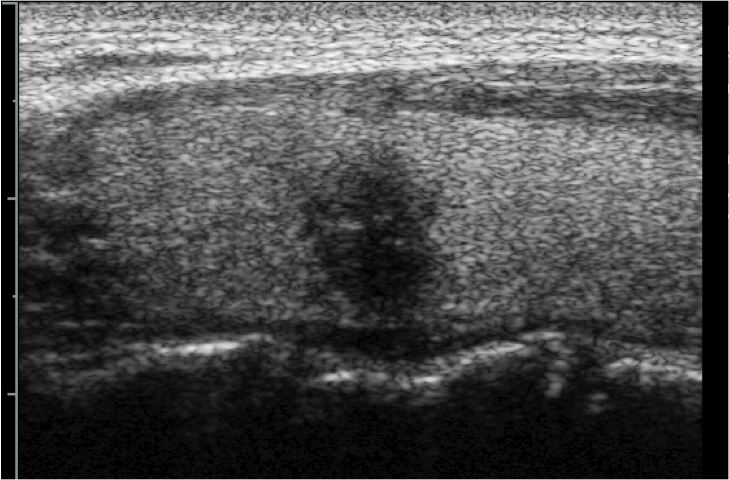

Nella tiroidite subacuta generalmente si riscontrano aree intensamente ipoecogene, a distribuzione zonale o lobare, la cui scansione ecografica provoca caratteristicamente dolore (fig. 2). La ripetizione dell’indagine ecografica nel tempo o in corso di terapia anti-infiammatoria consente di evidenziare cambiamenti nella localizzazione ed estensione delle aree di flogosi (9,10).

Figura 2. Tiroidite subacuta: a sinistra istmo e regione para-istmica destra, a destra lobo destro.